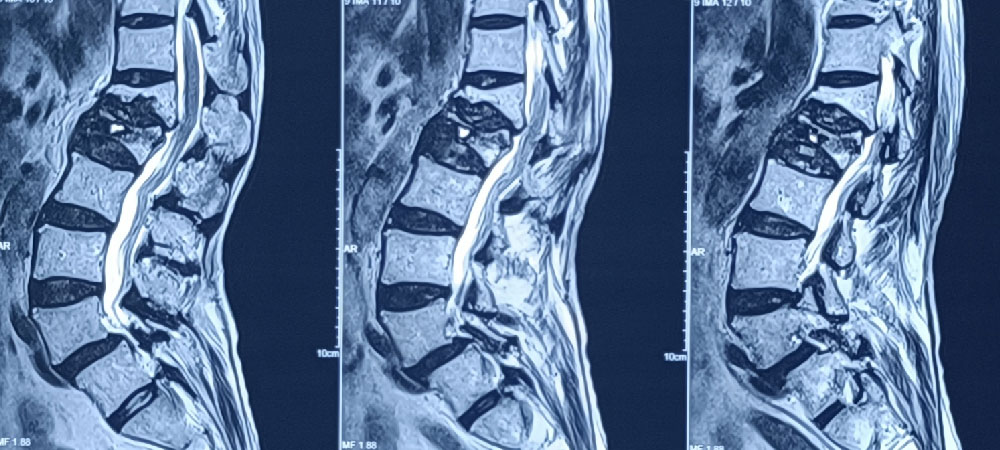

Leading spine surgeon in North Bengal & Siliguri, specializing in minimally invasive techniques for effective, faster recovery. With easier access to advanced dental technologies, you can now get personalized care plans for spinal conditions, chronic back pain, and disc issues.

Expert in diagnosing and treating complex spinal conditions with the latest surgical techniques.

Dr. Mayukh Guha, an experienced spine surgeon in Siliguri, offers expert diagnosis and advanced minimally invasive treatments. He is committed to delivering personalized care for various spinal conditions.

Using the latest spine surgery tools and techniques, Dr. Guha ensures precise treatment tailored to each patient's unique needs. At the best spine clinic in Siliguri, North Bengal, he offers minimally invasive procedures that promote faster recovery and lasting relief.